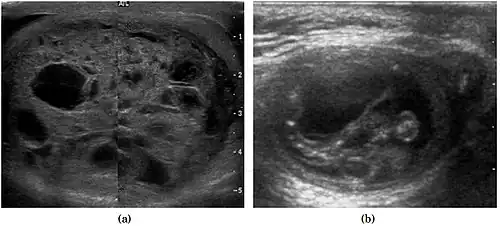

Fig. 5. Teratoma. A plaque-like calcification with acoustic shadow is seen in the testis. -

Fig. 6. Mature cystic teratoma. (a) Composite Image. Mature cystic teratoma in a 29-year-old man. Longitudinal sonography image of the right testis shows a multilocular cystic mass. (b) Mature cystic teratoma in a 6-year-old boy. Longitudinal sonography of the right testis shows a cystic mass containing calcification with no obvious acoustic shadow.